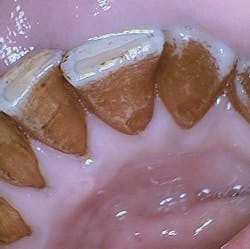

The patient in the image appearing with this column is scaled every four months because of the heavy stain on his teeth. Since he is a professional, he is very cognizant of his appearance when meeting with clients and makes certain that he arrives for his scheduled appointments.

George has stain on his teeth due to the fact that he drinks Darjeeling tea throughout the day, usually five to seven cups of strong tea. Darjeeling tea is highly flavored and is a favorite type of tea in India. It is often used in Chai tea that is popular in the United States as well.